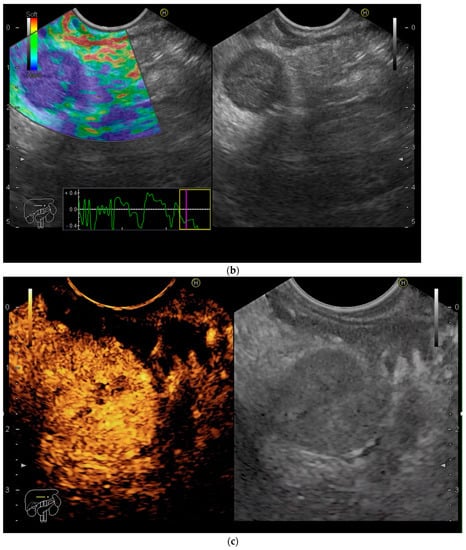

A 61-year-old male presented to the gastroenterology department with involuntary weight loss and upper abdominal pain. The patient was suffering from hypertension and type 2 diabetes mellitus, for which he was taking calcium channel blockers, an angiotensin receptor blocker and insulin. He had undergone left nephrectomy for RCC 6 years previously. Physical examination revealed an overweight patient with a postoperative abdominal scar and orthostatic hypotension. Laboratory examinations revealed mild normocytic anemia, elevated HbA1c and a decreased glomerular filtration rate. A CT-scan revealed a 6/5 cm hyperenhancing mass in the head of the pancreas, with consecutive dilatation of the common bile duct, and a 28/18 mm lesion with similar enhancing pattern in the gallbladder (Figure 2a,b), suggestive of metastasis, considering the RCC history. EUS-FNB of the pancreatic mass confirmed the diagnosis of RCC metastasis. Cholecystectomy and treatment with tyrosine kinase inhibitors were recommended.

(a) Contrast-enhanced computed-tomography scan showing hyperenhancing mass in the head of the pancreas, with consecutive common bile duct dilation. (b) Contrast-enhanced computed-tomography scan showing hyperenhancing mass in the fundus of the gallbladder.